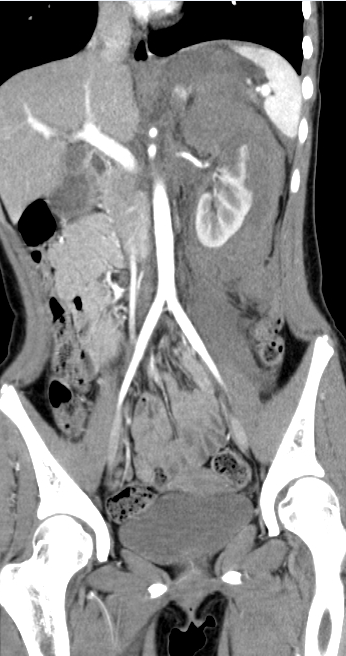

大范围低剂量CTA成像

采用业内最先进液态金属轴承技术的超大热容量球管,结合独有的低千伏、低毫安成像模式,天河640可实现冠脉、主动脉、下肢动脉等全身各部位大范围扫描、微辐射剂量的检查。低千伏扫描模式有效降低辐射剂量、对比剂总量、对比剂浓度、对比剂注射速率,降低肾功能不全受检者增强检查风险、减少对比剂外渗风险、并可大幅度提升增强检查碘对比剂对比度,提升强化效果;同时,系统还可根据不同患者体型和扫描协议自动推荐扫描管电压,在降低患者扫描剂量的同时,优化对比度噪声比。

图片说明:肺动脉+主动脉全程+下肢动脉大范围一次扫描成像。